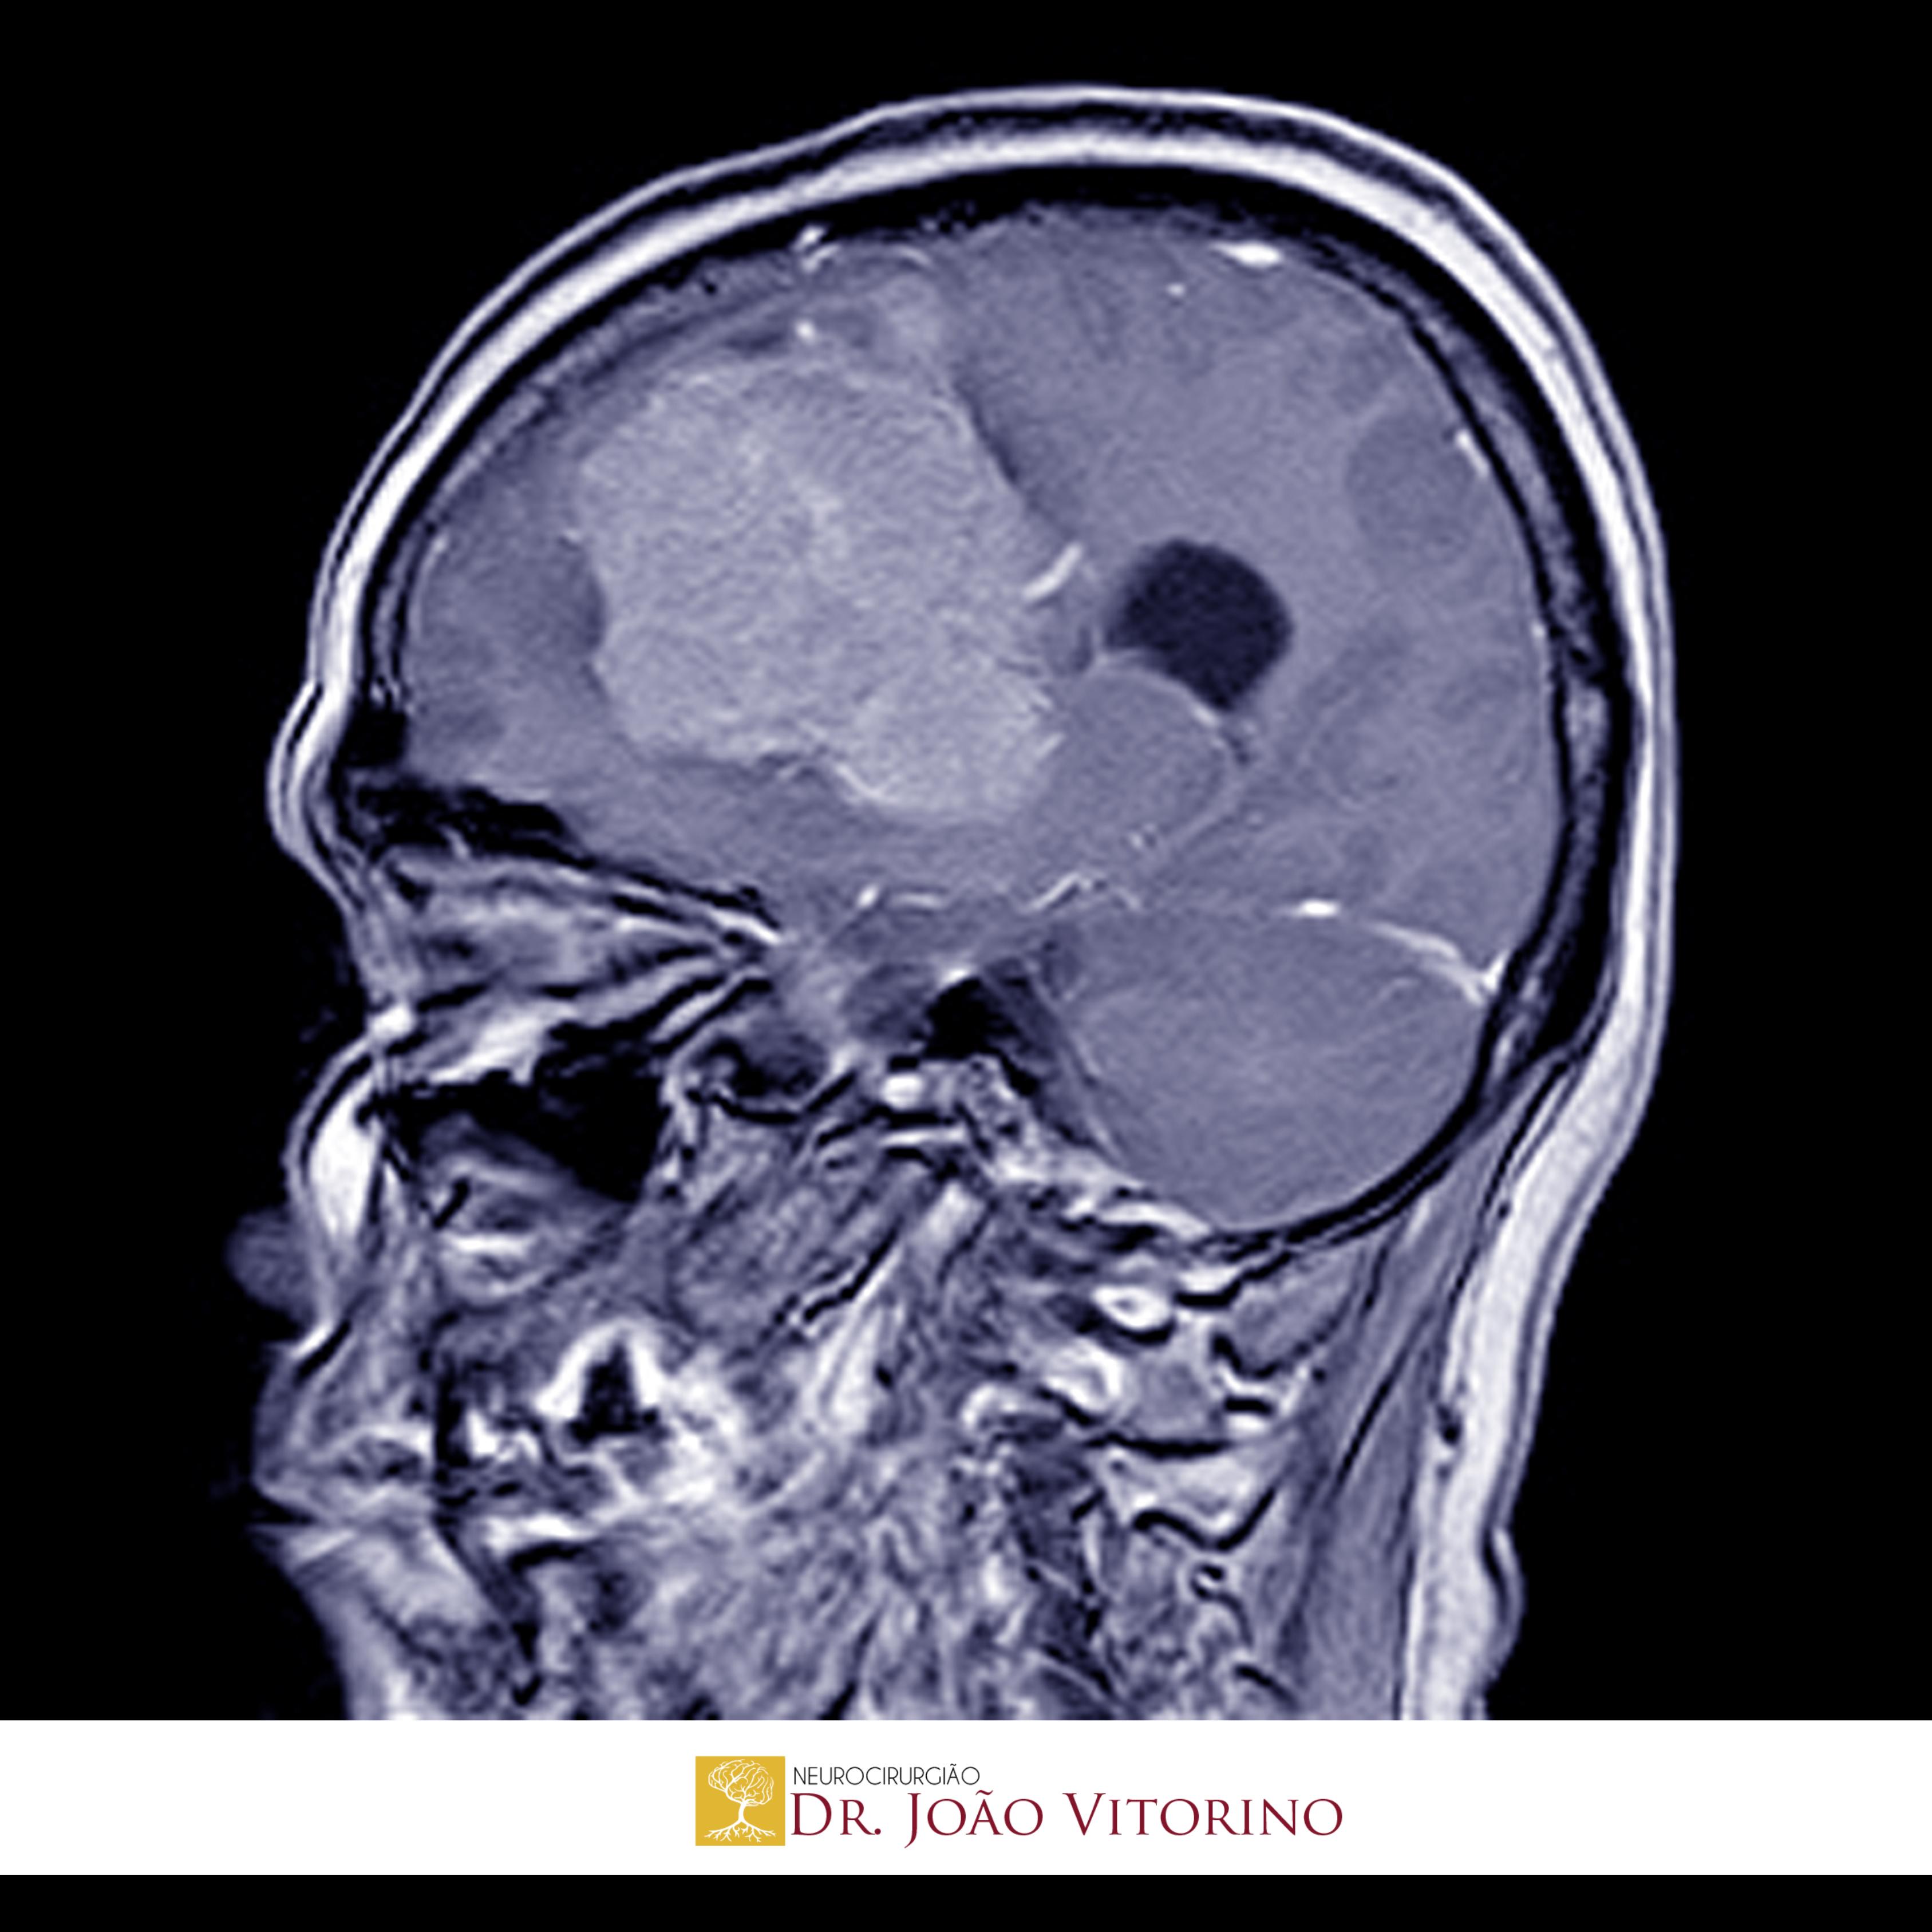

Avanços no Tratamento do Hemangioblastoma

O hemangioblastoma é um tumor vascular benigno do sistema nervoso central (SNC), mais frequentemente localizado no cerebelo, tronco encefálico e medula espinhal. Apesar de seu